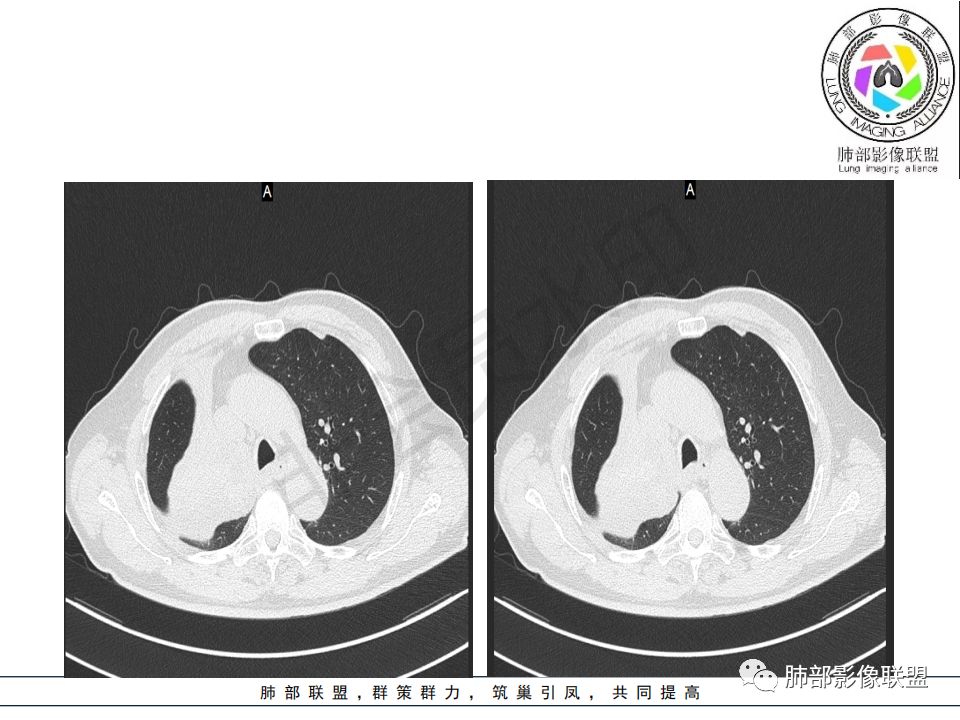

病理结果:腺癌,考虑来源消化道

说在后面的话:

1.右肺上叶较大块影,密度不均,轻度强化并见低密度区,所属支气管截断并腔内突入,是符合肺鳞癌的影像学特征和生物学行为的。

2.胃癌常会首先胃旁淋巴结、腹主动脉淋巴结转移,肝脏血行转移,以及双肺多发转移,本例孤立右肺上叶病灶巨大,多有不符。

3.胃癌多血供,患者肺内病灶轻度强化。

4.内镜取材不足的可能性是存在的。